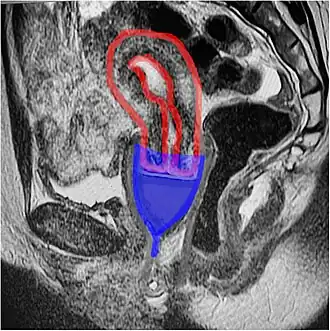

An MRI showing a bell-shaped menstrual cup in place; cup in blue, uterus in red. The ectocervix (the portion of the cervix that protrudes into the vagina) sits inside the cup. Sagittal plane.

While many diagrams show bell-shaped menstrual cups very low in the vagina, with the vagina gaping open, in-vivo imaging shows that the cups sit high, with their rim around the cervix, and the vagina squishes shut below the cup, sealing it inside the body.[7]